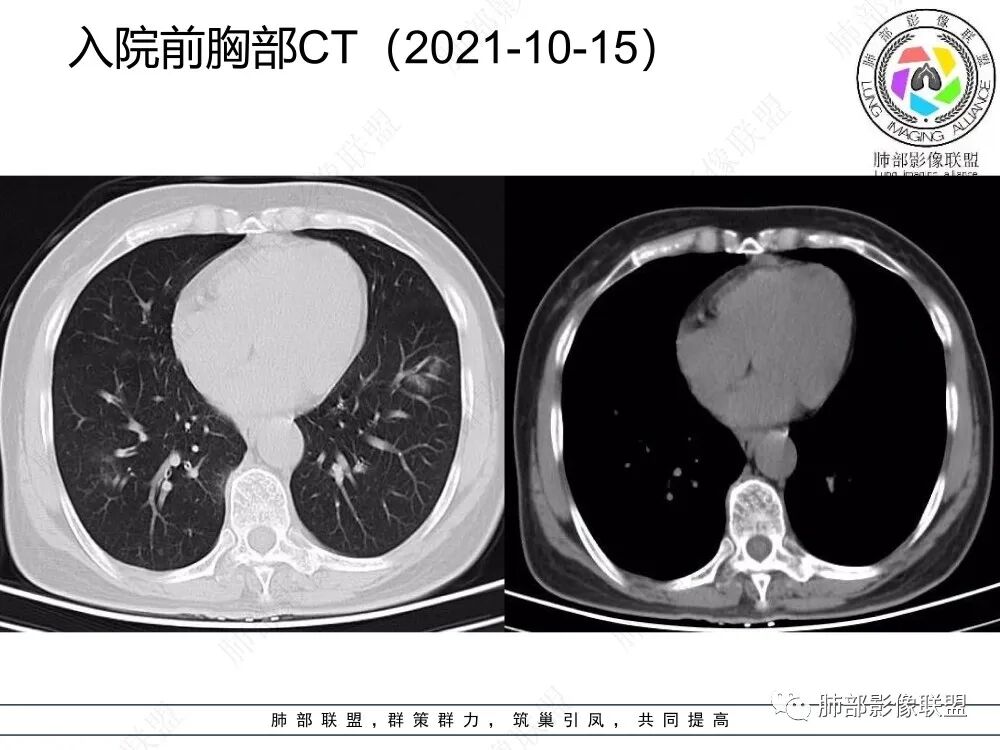

1、老年女性,急性病史,以咳嗽咳痰伴发热就诊,白细胞不高,肺炎支原体阴性,C反应蛋白增高,提示存在感染性病变。

2、CT表现为两肺下叶结节影、斑片影、磨玻璃影,沿支气管血管束分布,部分支气管壁显示增厚。粗略一看部分病灶内似可见“细网格影”,但是仔细观察,可发现此“细网格影”不同于我们常见的“细网格影”,尤其是右肺下叶病灶,可以观察到病灶内部的网格上有高密度结节感或颗粒感,部分层面见“反晕征”,且反晕的边缘亦可观察到结节感。未见胸腔积液。